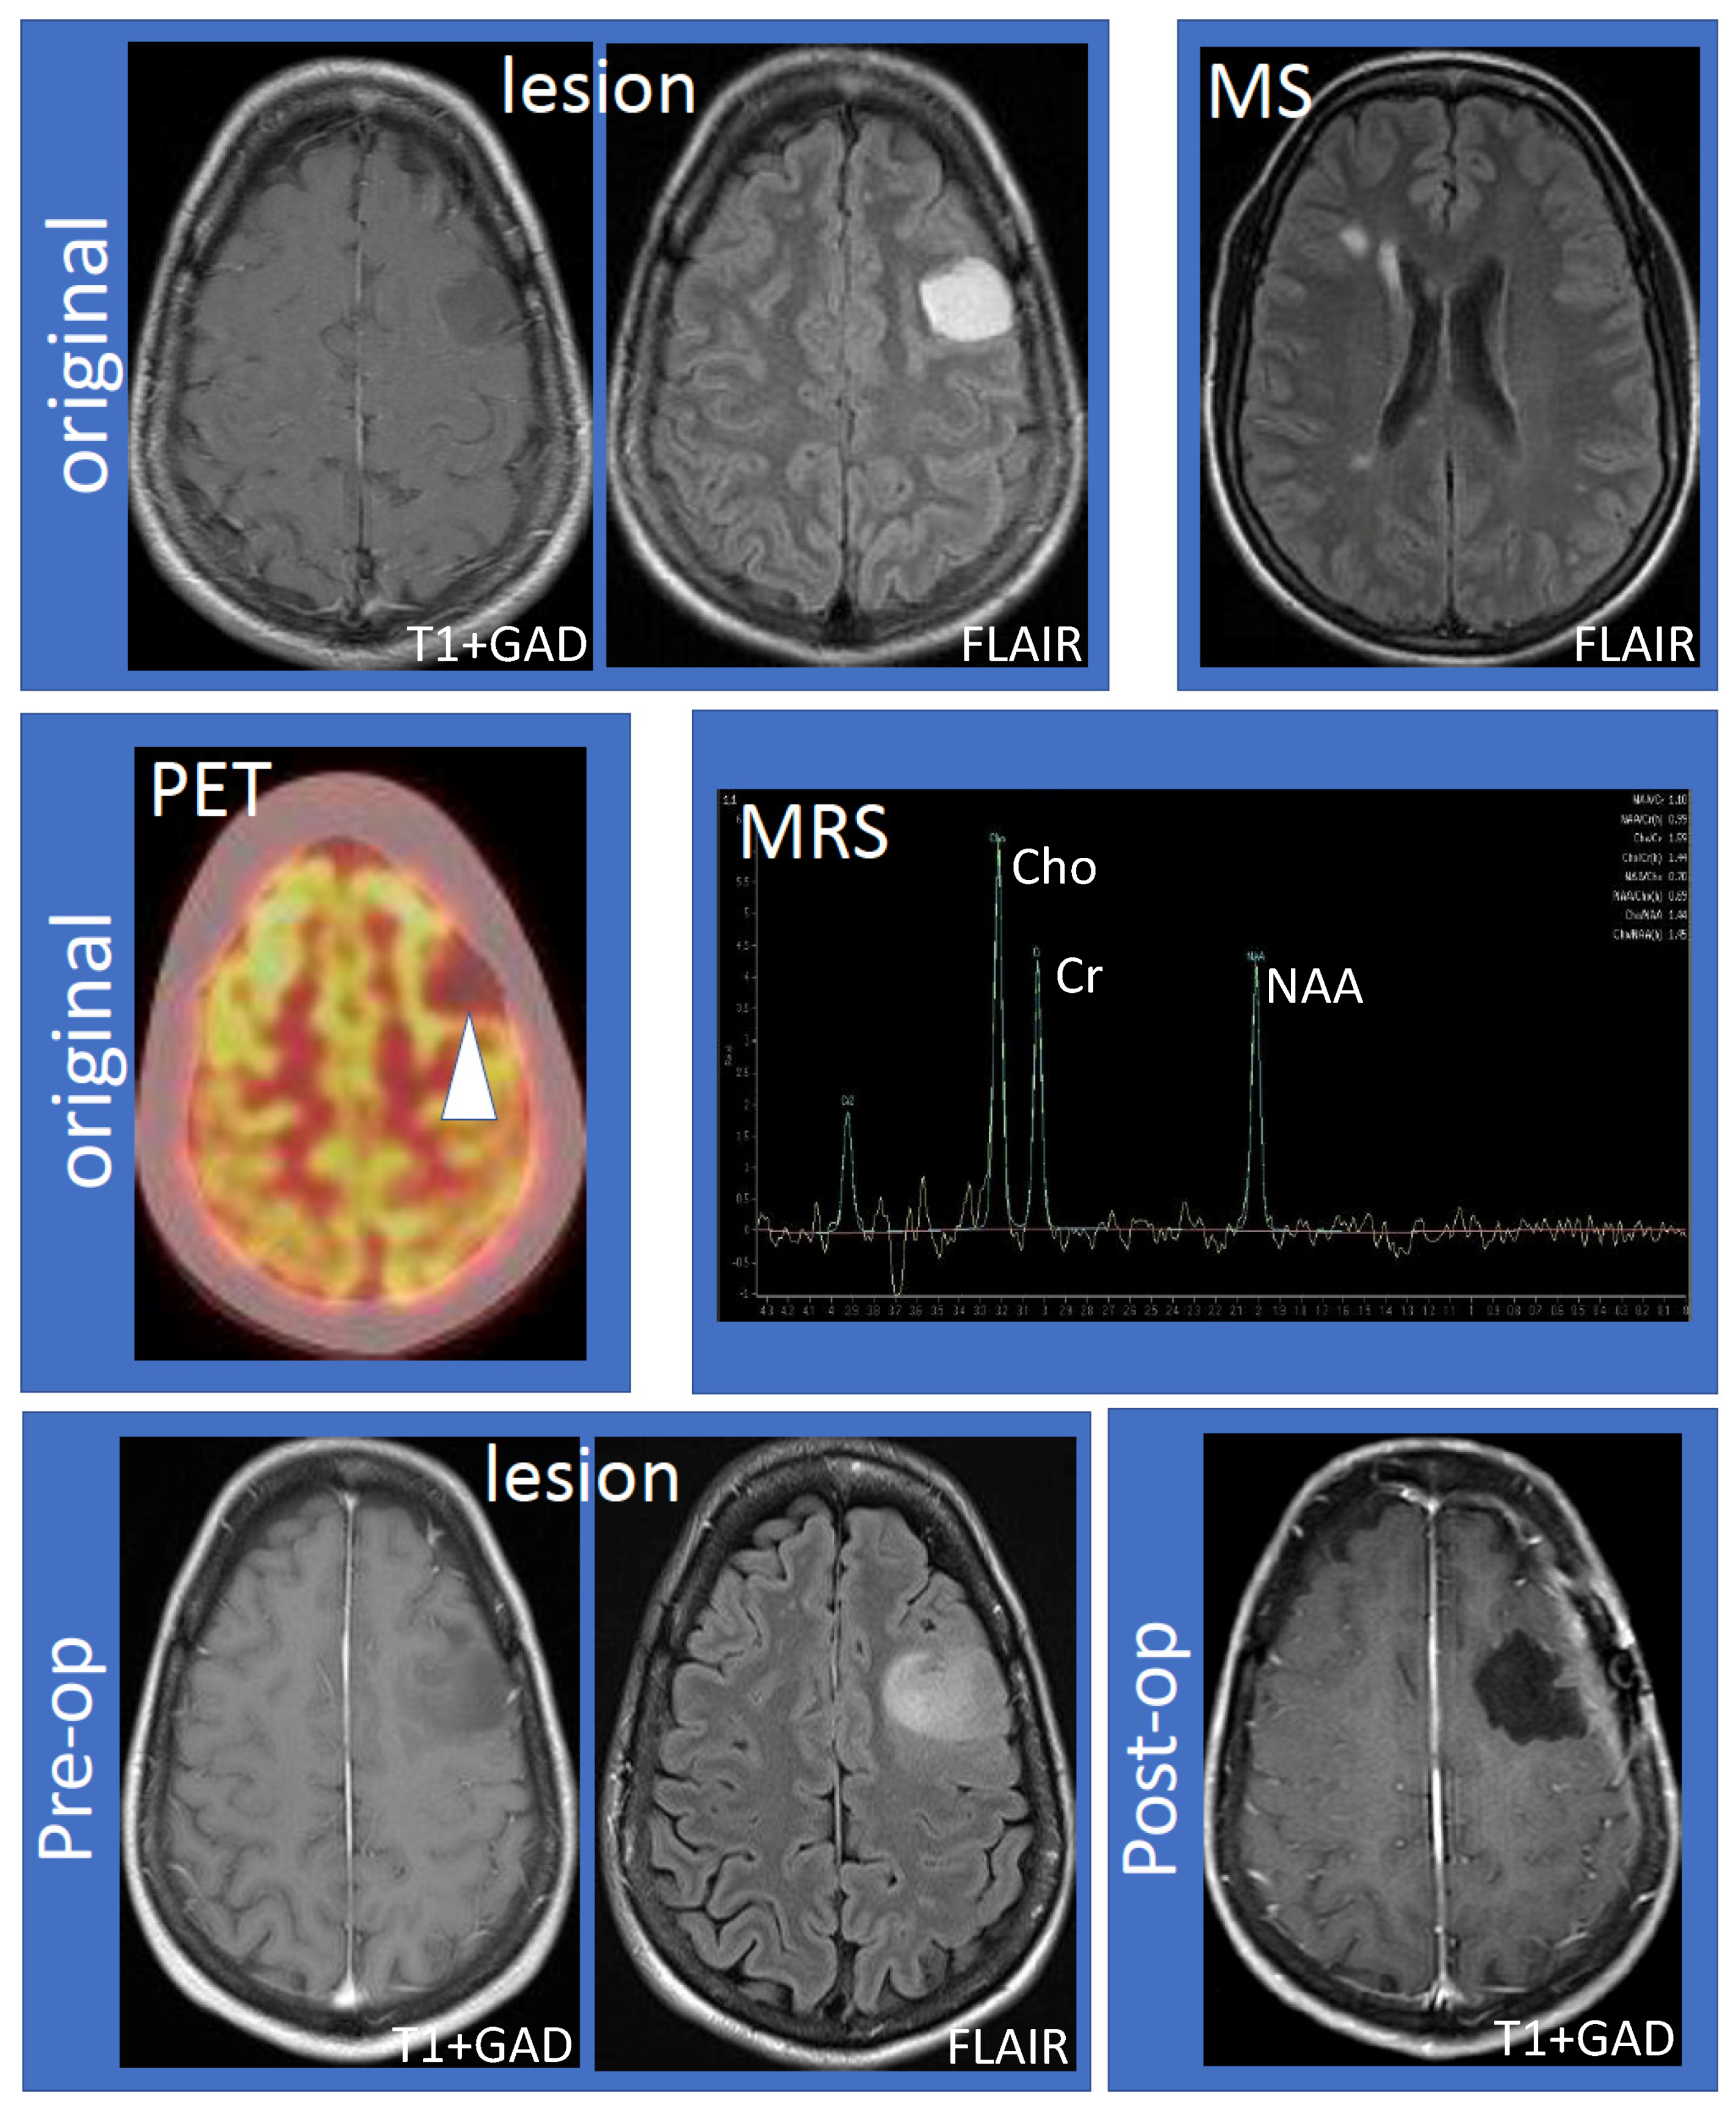

The 41-year-old female (non-smoker with a history of ulcerative colitis and celiac disease) had the onset of her MS 14 years ago, characterized by sensory symptoms of the lateral three fingers of the right hand, which resolved completely over several months. Seven years later, she experienced a second relapse characterized by paresthesias to her right hand, which spread to the medial aspect of her right arm, torso, leg, and toes. Following the second attack, she was diagnosed with RRMS based on MRI and clinical criteria. The initial MRI showed a large lesion (hypointense, non-enhancing on T1; hyperintense on fluid-attenuated inversion recovery (FLAIR) imaging) within the left frontal hemisphere involving the cortex and adjacent white matter (Figure 1, top row, “lesion”). Multiple white matter lesions were seen in both cerebral hemispheres compatible with MS (Figure 1, top row, “MS”). Focal hyperintensity was also observed in the right dorsal column of the cervical spinal cord at the C5–6 vertebral body level. Further evaluation by fluorodeoxyglucose positron emission tomography-computed tomography (FDG PET-CT) showed that the lesion was hypometabolic (Figure 1, middle row, “PET”). Magnetic resonance spectroscopy (MRS) revealed decreased N-acetylaspartate (NAA) with an NAA/creatine (Cr) ratio of 1.1 (Figure 1, middle row, “MRS”). The choline (Cho) was elevated, the Chol/Cr ratio was high at 1.59, and the Cho/NAA was 1.44. A significant lactate peak was not demonstrated. Neurosurgical and neuroradiological consultation suggested that the lesion in the left frontal hemisphere was consistent with a TDL in MS. Glatiramer acetate was initiated and the patient remained stable for the next four years without relapse or MRI activity. The patient had an expanded disability status scale (EDSS) of 1.0 since her diagnosis, without any evidence of confirmed disability progression or functional decline. The left frontal hemispheric lesion was followed over four years with serial MRI scans, which showed that the lesion increased in size with a mild mass effect involving the left middle frontal gyrus and underlying white matter (Figure 1, bottom row, “lesion”). There was interval stability of demyelinating plaques in the brain and cervical spinal cord. Neurosurgery was reconsulted and an elective left frontal awake craniotomy with the total resection of the lesion was carried out. Tissue diagnosis revealed primary left frontal diffuse astrocytoma (WHO grade II), 1p19q non-co-deleted, O6-methylguanine-DNA-methyltransferase (MGMT) methylated (46.5%), isocitrate dehydrogenase 1 (IDH1) R132H mutation, and loss of ATRX (alpha-thalassemia/mental retardation X-linked) expression. Post-operatively the patient experienced mild expressive dysphasia and was discharged on a tapering dose of dexamethasone. Following surgery, the patient received radiotherapy (54 Gray in 30 fractions) followed by temozolomide (6-cycle regime) for six months as an adjuvant treatment. She experienced a seizure, which was successfully treated with levetiracetam (750 mg) orally twice daily. She was on glatiramer acetate (20 mg) subcutaneously once daily throughout her course, and her MS remained stable by clinical and MRI criteria. Follow-up MRIs showed no recurrence of the glioma (Figure 1, bottom row, “post-op”) and stable white matter, ovoid, and periventricular lesions consistent with MS.

Figure 1.

Work-up and progression of the left frontal lobe lesion. The top row shows the large, non-enhancing lesion distinct from MS lesions (left to right: T1 following gadolinium administration (T1 + GAD) and fluid attenuated inversion recovery (FLAIR) showing the lesion; FLAIR showing MS lesions). The middle row shows hypometabolism of the lesion using fluorodeoxyglucose positron emission tomography–computed tomography imaging and results of magnetic resonance spectroscopy (MRS). MRS values are as follows: N-acetylaspartate (NAA)/creatine (Cr) 1.10, NAA/Cr(h) 0.99, choline (Cho)/Cr 1.59, Cho/Cr(h) 1.44, NAA/Cho 0.70, NAA/Cho(h) 0.69, Cho/NAA 1.44, and Cho/NAA(h) 1.45. The bottom row shows that the lesion increased in size compared to the original MRI (“pre-op”) and successful resection of the lesion (“post-op”). Abbreviations: MS: multiple sclerosis; PET: positron emission tomography; MRS: magnetic resonance spectroscopy; Pre-op: pre-operative; Post-op: post-operative.

Differentiating between TDLs and brain tumors is challenging, particularly in the early stages of brain cancer. In this patient, diagnostic delay likely occurred because she was clinically stable, the lesion occurred in the setting of MS diagnosis (early in disease) and multiple imaging techniques could not adequately distinguish between TDL and early glioma. In addition to standard brain MRI imaging, the patient underwent FDG-PET-CT, which was hypometabolic (favoring TDL), and MRS, which was equivocal (Cho/NAA ratio = 1.44; >1.72 highly correlates with high-grade glioma [3]). The co-occurrence of glioma and MS in the same patient is uncommon, and most of the previously reported cases had high-grade astrocytic tumors that developed after MS diagnosis [4].